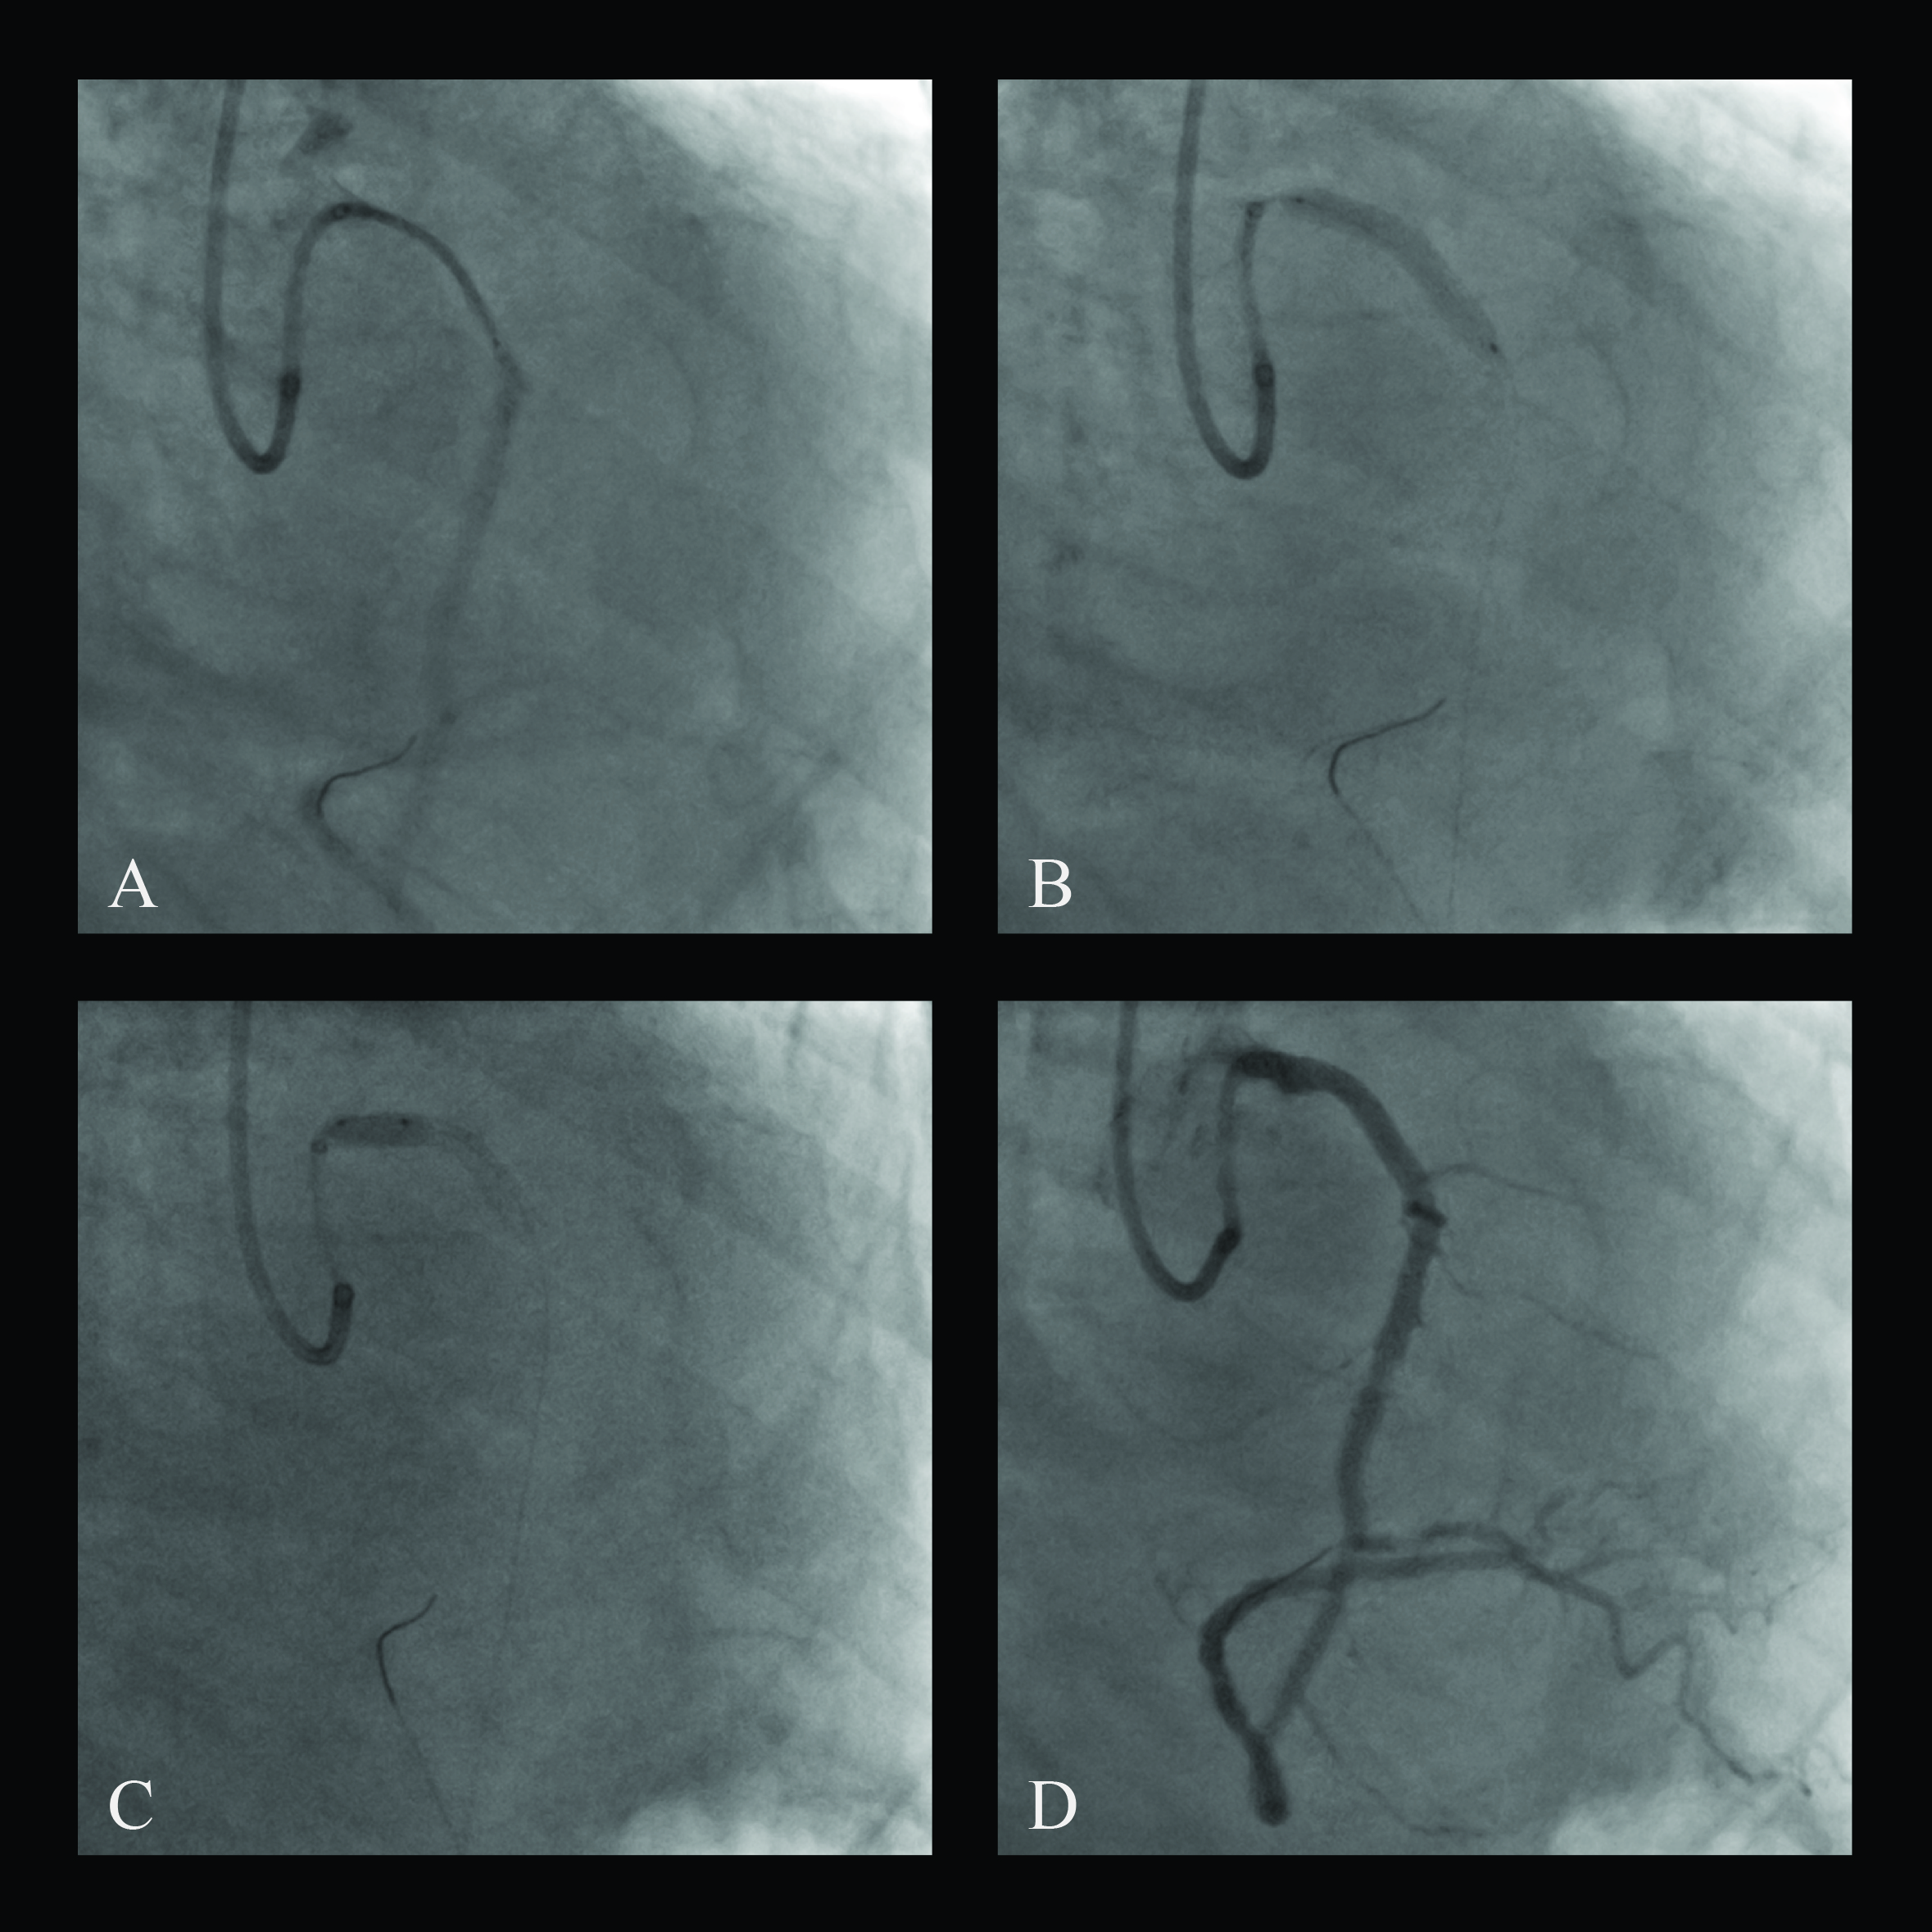

A 3.5 x 26-mm drug-eluting stent was implanted and post-dilated in the intramural RCA with a good result (Figure 3). The clinical course was uneventful. After 12 months, the patient was asymptomatic and coronary computed tomography confirmed the good patency of the implanted stent (Figure 4).